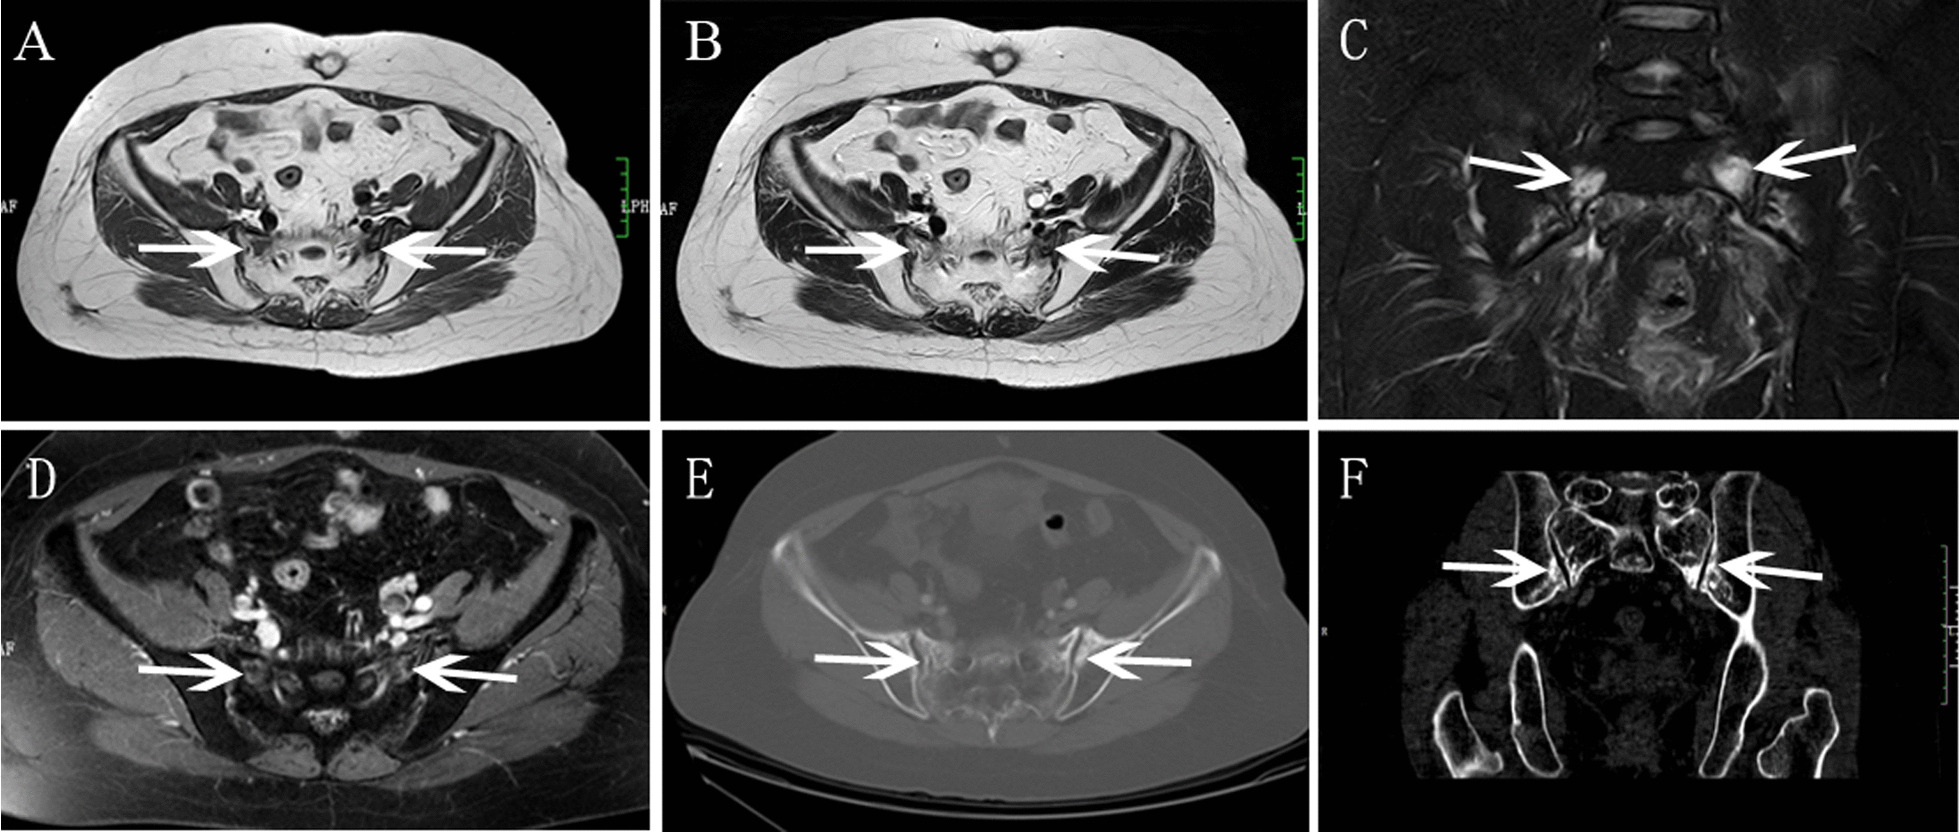

Nine patients (31.0%) developed with unilateral SIFs (Figs. 1 and 2), and nineteen patients (69.0%) with bilateral SIFs (Figs. 3, 4 and 5). In total of 15 patients (53.6%) developed with concomitant fractures, include L5 fractures (14.3%, 4 patients) (Fig. 3), acetabulum fractures (17.8%, 5 patients) (Fig. 3), ilium fractures (21.4%, 6 patients) (Fig. 4) and pubis fractures (14.3%, 4 patients) (Fig. 5).

Fig.5.

Bilateral SIFs had coexistent pubis fracture in a 63-year-old woman with cervical cancer after radiotherapy. A BS showed bilateral sacrum increased accumulation (white arrow) as an “H-sign”, and left pubis increased accumulation (red arrow). B Axial T1WI showed hypointensity. C Coronal FS-T2WI showed severe bone marrow edema. D Axial enhanced T1WI showed contrast enhancement in bilateral sacrum. E Axial enhanced T1WI showed enhancement with fracture line